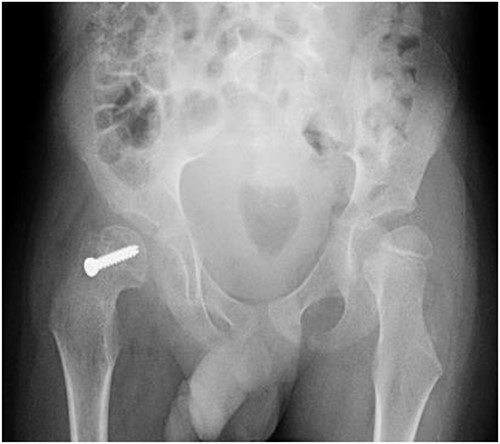

Pelvic anterior–posterior radiograph showing coxa valga deformity in the left hip.

A 5-year-old independent ambulatory Middle Eastern boy with CP who was born preterm and developed grade III intraventricular haemorrhage and periventricular leucomalacia and was on AEDs, including valproic acid (VPA) and levetiracetam (LEV), for >3 years and was controlled over the last year (no history of seizure attack) presented to the emergency room (ER) with right hip pain and inability to bear weight for 4 weeks; the patient had no history of fever or trauma. Physical examination shows a thin, the weight is 12 kg, the height is 101 cm, vital signs within the normal range, tenderness over the right hip, and external rotation of the right hip, with restricted hip mobility. A radiological study was performed ~3 months before the patient presented to the ER for follow-up examination of a left hip coxa valgus deformity with no apparent abnormalities in the right hip (Fig. 1). Initial imaging studies conducted in the ER showed an anterior–posterior view of the pelvic radiograph, revealing Klein’s line [13] not intersecting the capital femoral epiphysis (Fig. 2), and frog-leg lateral view radiograph of the right hip (Fig. 3) confirmed SCFE and Southwick’s slip angle [13] of ~50° (moderate). Laboratory findings were clear for endocrine and renal diseases or infection, except for low vitamin D (total 25-OH Vitamin D: 43.4 nmol/L), suggesting vitamin D insufficiency. The diagnosis was confirmed with clinical and radiological studies as right-sided unstable SCFE requiring surgery. Surgical intervention was performed with percutaneous in situ fixation using a single fully threaded 4.5-mm cannulated screw (Fig. 4). Postsurgical rehabilitation included non-weight-bearing right lower extremities for 6 weeks. Regular follow-up with serial radiology studies showed stable fixation with no migration of screw or further slippage at 6 weeks (Fig. 5) and 3 (Fig. 6), 15 (Fig. 7), and 36 months (Fig. 8). During follow-up, a painless range of motion in the right hip was observed, with full weight-bearing and resumption of his usual activities with no complaints.